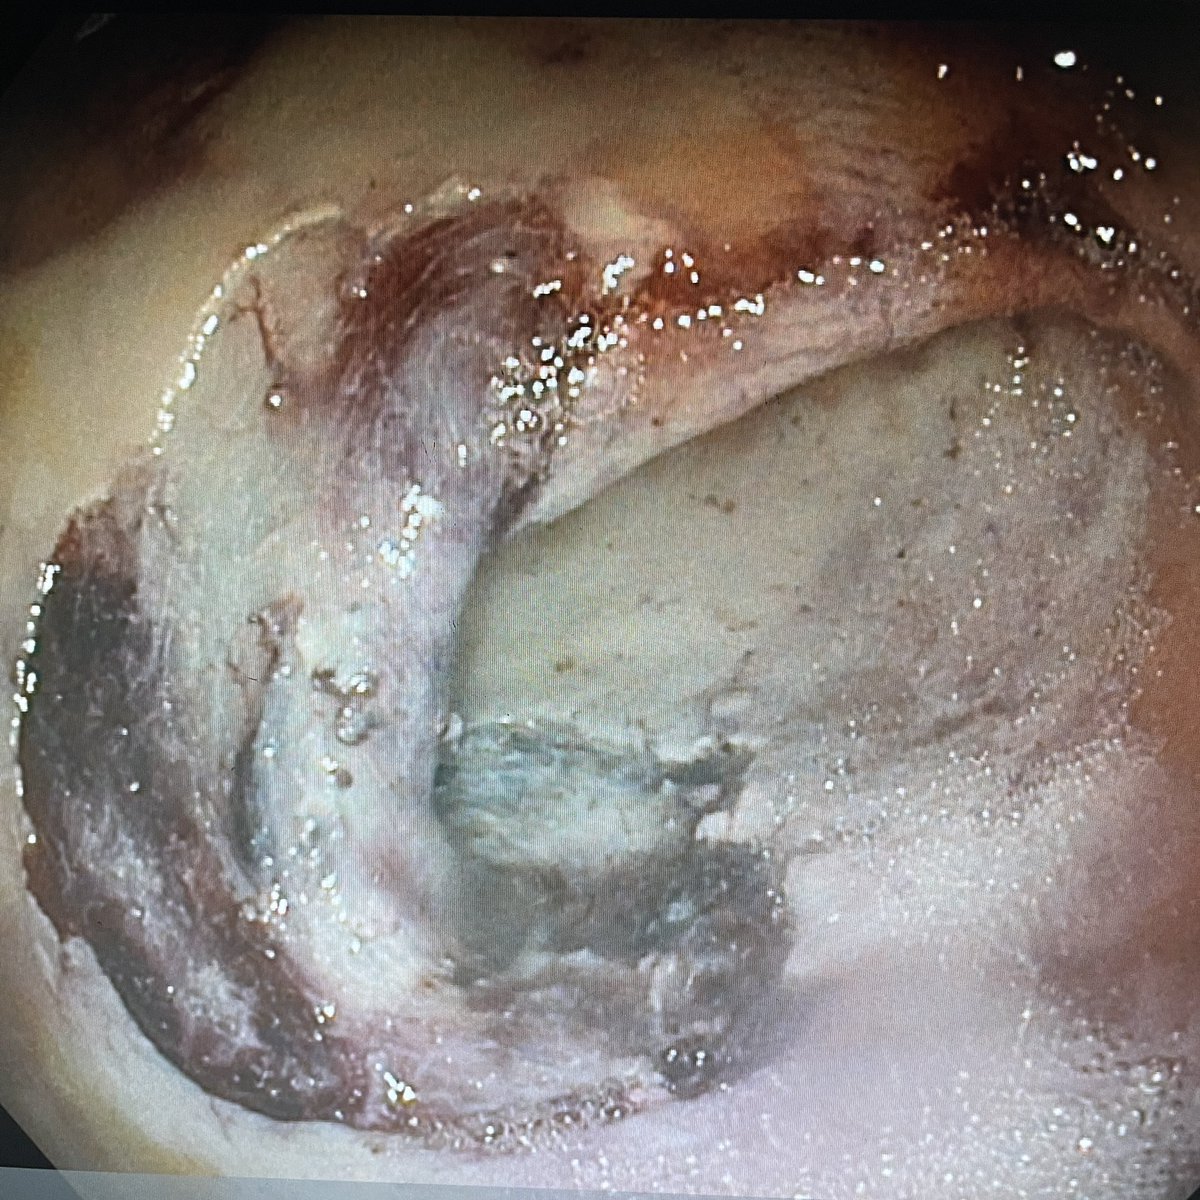

Distal duct diameter relative to size of stone a determinant of “difficult stones”. For stones above a stricture suggest use of @cookmedical fcSEMS to remodel before attempt at stone clearance. See how @gwebster_endo and @tmenabawey did it. Join us Thursday 1800 GMT for GL: LIVE

@GastroLearn @CookMedical @TMenabawey Stones above strictures a real challenge! We’ll be discussing optimal management (and all things stones!) 1800-1830 GMT Thurs April 14th ‘Between a Rock and a Hard Place’ Join free @GastroLearn #GITwitter @BritSocGastro @ESGE_news @helpatologist @drkeithsiau @EndoscopyNow